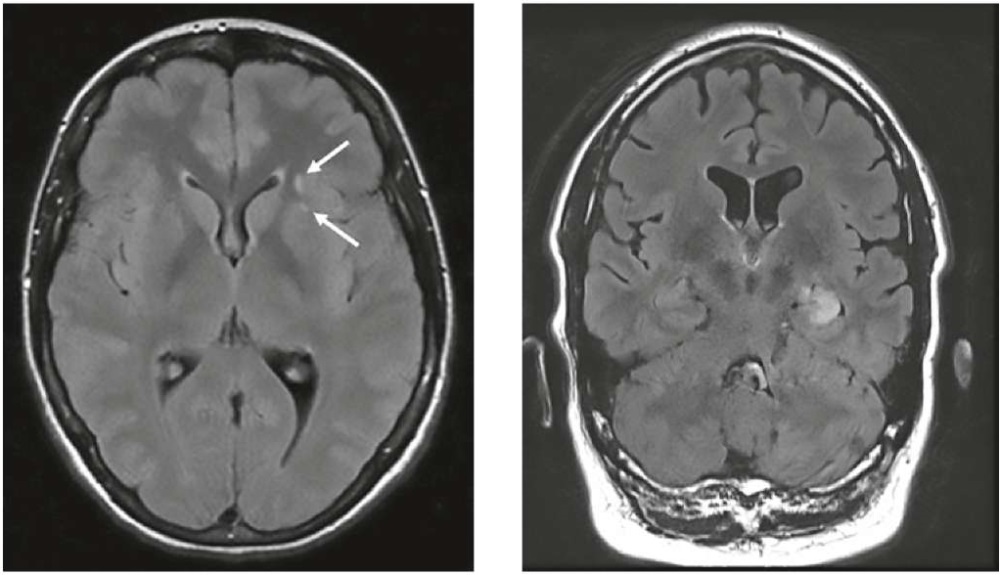

В целом при NMDAR-энцефалите возможны самые различные паттерны МРТ-поражений. Наиболее характерными являются неспецифические гиперинтенсивные поражения белого вещества (40% случаев), преимущественно лобной (рис. 1), реже височной и теменной долей. Также наблюдаются изменения коркового серого вещества, поражения глубоких структур серого вещества (базальные ганглии, гиппокамп, гипоталамус), поражения ствола мозга или мозжечка. При этом в острой стадии вовлечение гиппокампа отмечается достаточно редко, в отличие от лимбического АИЭ — при LG1-энцефалите односторонняя или двусторонняя T2/FLAIR-гиперинтенсивность медиальных отделов височных долей выявляется в 70% случаев (рис. 1) [14].

Рисунок 1. Слева — два небольших неспецифических T2/FLAIR-гиперинтенсивных очага в левой лобной доле при NMDAR-энцефалите; справа — T2/FLAIR-гиперинтенсивность в медиальных отделах левой височной доли при LG1-энцефалите в стадии лимбического энцефалита [14].

Figure 1. Left — two small non-specific T2/FLAIR-hyperintense lesions in the left frontal lobe in NMDAR-encephalitis; right — T2/FLAIR-hyperintensity in the left medial temporal lobe in LG1-encephalitis at the stage of limbic encephalitis [14].